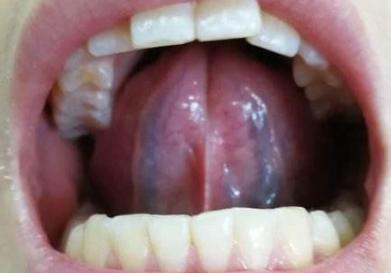

调理这种血瘀舌最有效的方法是温阳化气,不然血府逐瘀丸吃多少年都没用! 患者舌底,黑黑粗粗两条血管,典型的血瘀舌,平时身上头痛,失眠,淤青难消,腿部干燥起皮,血府逐瘀没什么效果。改用温阳方,着重温阳化气,散寒祛瘀,患者的情况得到了明显的改善。 其实问题的重点就在患者的舌面: 舌面除了有紫色的瘀滞点外,舌面舌苔白白腻腻,舌中凹陷,这是典型的阳气不足,不能化气。患者同时兼具怕冷手脚凉,少气懒言,肚子胀不消化等问题。 黄帝内经上讲,气为血之帅,气不足,推不动血,血根本就流动不起来,时间一长特别容易形成瘀阻,堵在脉络里边。 这种时候,如果只盯着淤血去清理,源头的阳气没补上来,效果可想而知。 根据患者舌象以及脉象综合开方:制附子,干姜,桂枝,当归,川芎,赤芍,黄芪,党参,炙甘草 核心原则:温阳散寒 + 活血化瘀,兼顾补气行血 温阳核心:制附子 (先煎减毒)、干姜、桂枝(温通阳气,散寒凝); 活血核心:当归 、川芎、赤芍 (活血通络,兼顾养血,避免活血伤正); 补气佐使:黄芪 、党参 (补气以推动血行,助阳气布散); 调和:炙甘草(调和诸药,缓附子之峻)。 如果相近问题,可以伸舌辨证。 以上为医学参考,具体问题需结合自身情况,辨证就医。